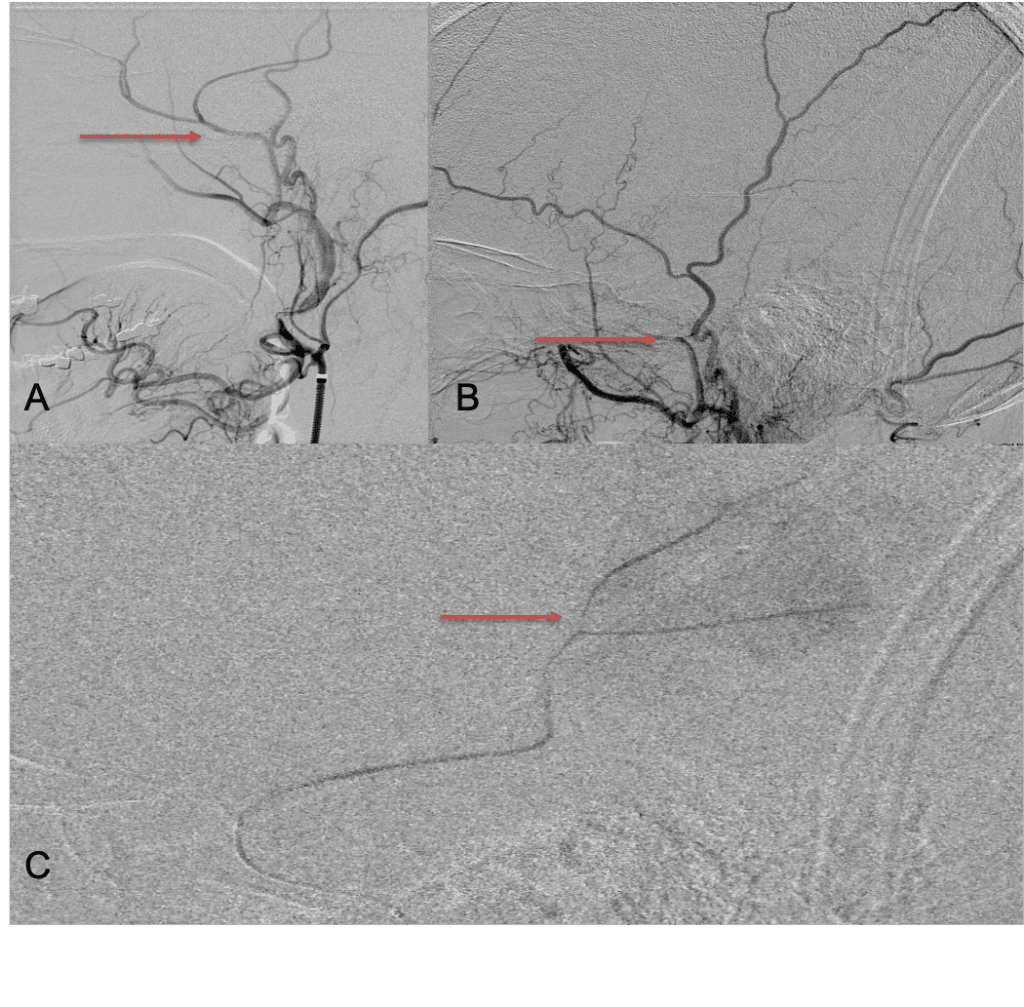

The patient agreed to receive minimally invasive treatment with Bilateral Middle Meningeal Artery Embolization, a new approach to promote resorption of chronic and subacute subdural hematomas in patients that are not improving with conservative measures or have contra-indications to surgical evacuation. Selective catheterization of the Middle Meningeal Artery is followed by transarterial embolization of the territory and inflammatory membranes that are felt to be secreting serosanguinous proteinaceous exceeding the capacity for resorption. MMA embolization was performed bilaterally in this patient. (Figure 2. A and B)

Figure 2. A) Initial right ECA angiogram ; B) Post MMA Embolization; C) Selective Embolization Of Middle Meningeal Artery Membranes using PVA particles (arrows).